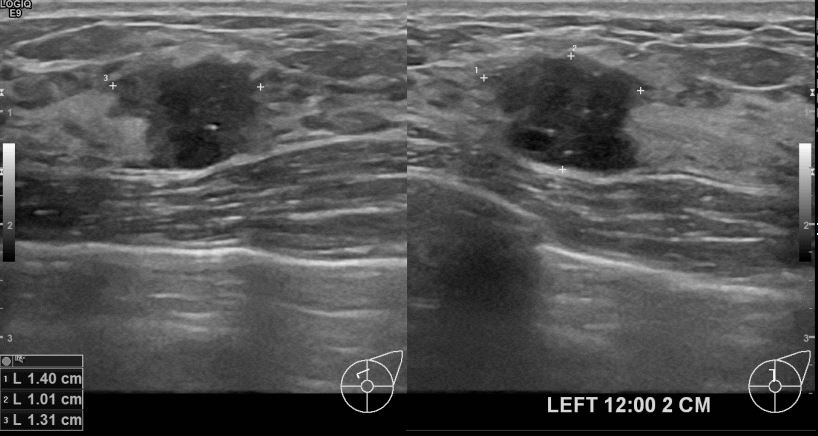

아산유외과 개원후 631번째 유방암 진단

상기환자 외부검사상 이상소견으로 내원하신 40대여성으로 좌측유방의 의심스러혹

조직검사시행해 유방암 진단되었읍니다